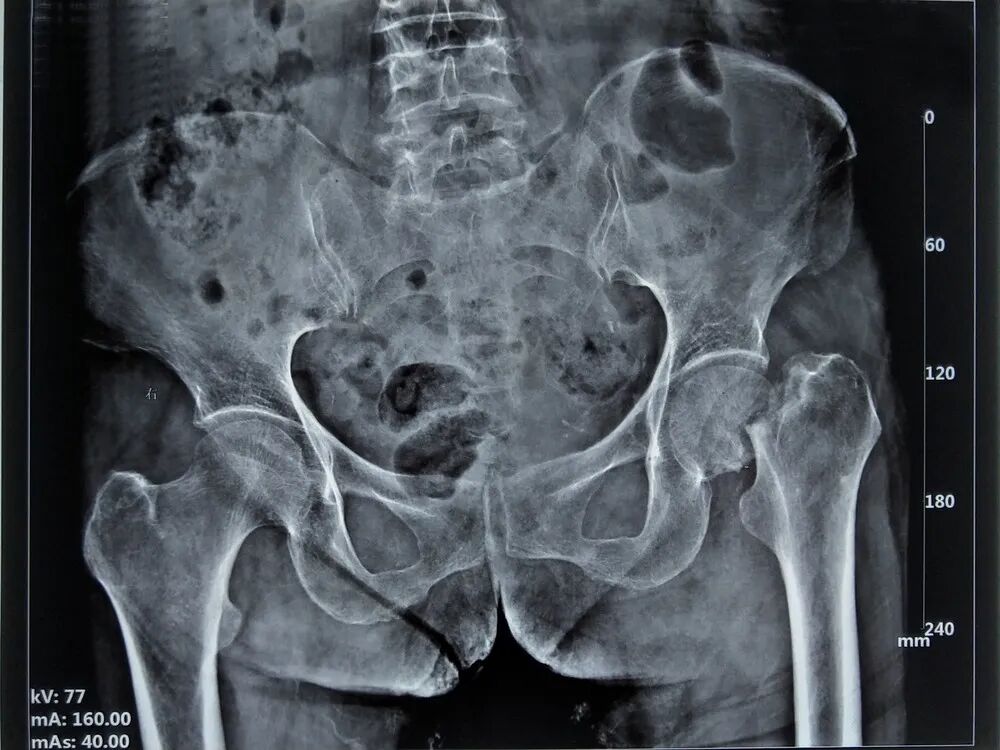

11月29日,柳位中医正骨医院邀请到了新乡医学院第一附属医院骨外科梁秋冬主任及其团队与鼎健医疗完美配合,完成了河南首台尚氏LDAA双动髋关节手术,手术过程顺利。尚氏LDAA双动髋关节手术主要针对侧卧位直接前入路(LDAA)治疗融合髋、低位髋、髋关节翻修以及合并脊柱后凸畸形等疑难病例的手术。

患者左髋部疼痛,肿胀,活动受限,随后到“下街卫生院”就诊,行DR片,左侧股骨颈骨折,随后又到柳位中医正骨医院就诊,行CT片,左侧股骨颈骨折,初步诊断为“左侧股骨颈骨折”。

现病史:6天前,患者下门台时踩空,致左髋部疼痛、肿胀、活动受限,无昏迷、恶心等症状,无胸腹不适,受伤过程能清晰回诉,随后到“下街卫生院”就诊,行DR片,左侧股骨颈骨折,随后又到我院就诊行CT片,左侧股骨颈骨折,为进一步治疗,来我院就诊,门诊以“左侧股骨颈骨折”收入我科。